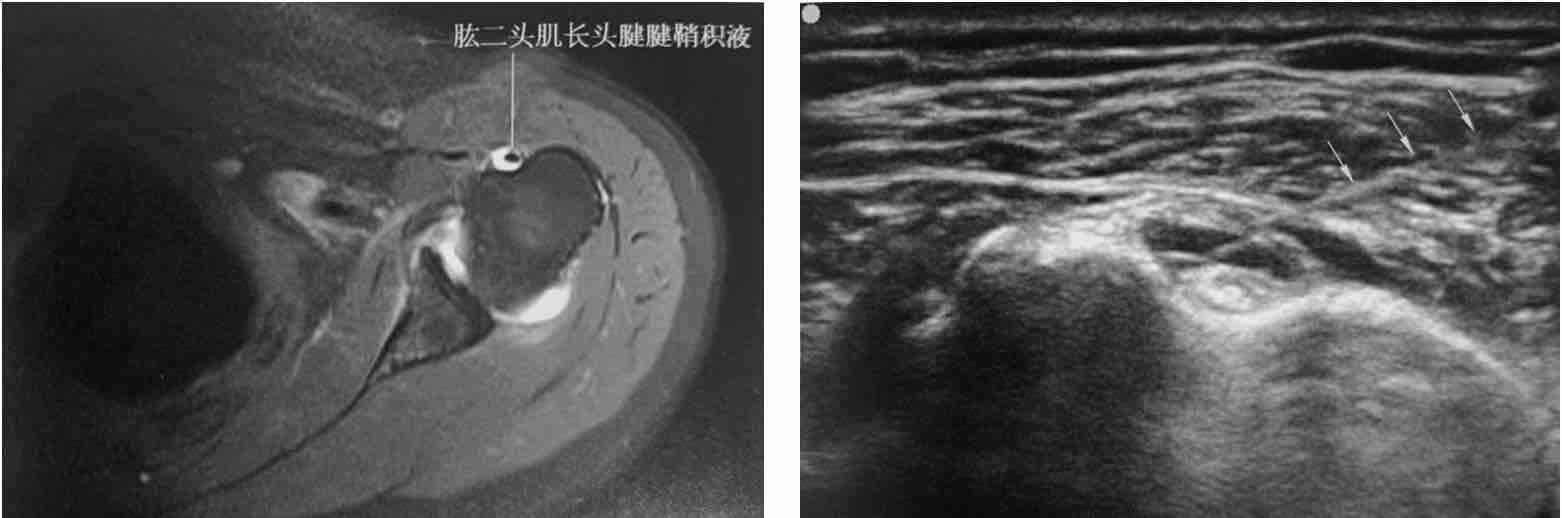

- 超声检查:发现肱二头肌长头腱关节囊外部分周围出现液性暗区或低回声区,而肩关节内无液性暗区。

超声检查显示位于结节间沟内的长头肌肌腱腱鞘增厚,回升减低(王月香-肌骨超声诊断)

MRI显示肱二头肌肌腱及腱鞘积液、超声引导下肱二头肌腱鞘穿刺抽液(杜冬萍-超声引导下疼痛注射治疗)